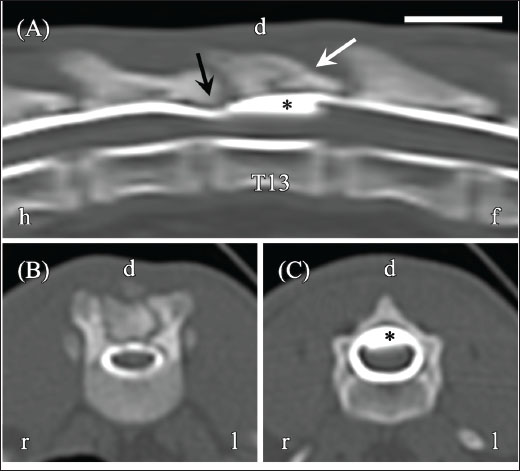

CT myelography was performed using an Alexion CT scanner (Canon Medical Systems, Otawara, Japan) to evaluate the relationship of the fluid-filled lesion (slice thickness, 1.0 mm; reconstruction kernel, FC30). Iohexol (Omnipaque 240) was administered via lumbar puncture at a dose of 0.4 ml/kg under CT guidance. Scans were obtained approximately 5 minutes after the injection. The contrast distribution and the presence or absence of extradural/intradural filling defects were assessed. A bone tissue window (window width, 3,000 HU; window level, 500 HU) was used for analysis. CT revealed thickening of the dorsal vertebral arch associated with the T13 fracture, but no vertebral misalignment. CT myelography showed no narrowing or rupture of the contrast medium column (Fig. 3A–C), suggesting an intramedullary lesion.

Fig. 3. CT myelography of the thoracolumbar vertebrae on day 1. (A) Sagittal reconstructed CT myelography shows no obvious spinal cord compression. (B) Transverse image at the T12–T13 level shows an intact contrast medium column without deformation. (C) Transverse image at the T13 level shows an expanded contrast medium column. Images were acquired using a bone tissue window (window width, 3,000 HU; window level, 500 HU). Orientation markers: h=head, f=foot, r=right, l=left. Scale bar=1 cm.